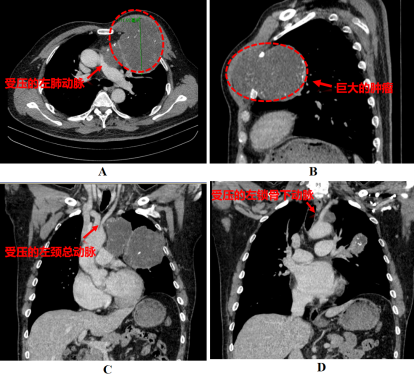

胸部CT显示

老范体内的肿瘤达11厘米,不仅体积巨大,还侵蚀了左侧第2-4肋骨,像馒头一样突出胸壁。更严重的是,肿瘤占据左侧胸腔及纵隔,还与主动脉、肺动脉主干、心包、神经紧密粘连。这种情况手术风险极大,稍有不慎就可能引发致命性大出血。